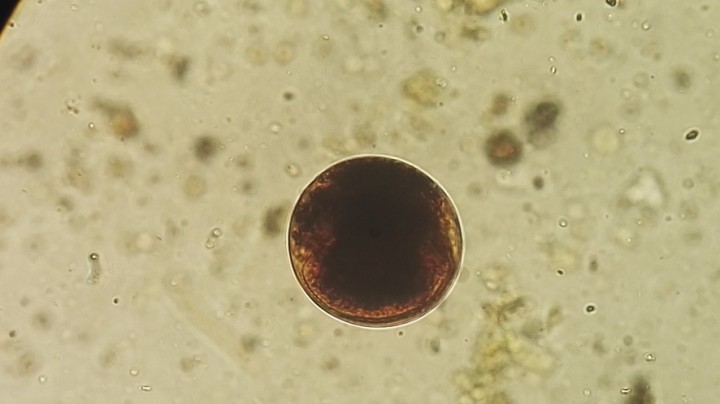

<p>Imagen de quiste de <em>Balantidium</em> sp. (Lugol, 100 x).</p>

Figura 5

Imagen de quiste de Balantidium sp. (Lugol, 100 x).

Aunque se han encontrado ciliados en todas las especies de tortuga analizadas, la prevalencia en T. graeca ha sido menor (significación estadística: p<0,000) que en las demás especies de tortugas. Los ciliados encontrados pertenecen a los géneros Nyctotheroides y Balantidium. En el caso de Nyctotheroides (Gemania según otros autores),[ Geimann QM, Wichterman R. Intestinal protozoa from galapagos tortoises (with descriptions of three new species). J Parasitol, 1937; 23 (4): 331- 347 ] se han encontrado trofozoítos y quistes de dos especies distintas, cuyas características morfológicas coinciden con las de N. kyphodes y N. teleacus, descritas en tortugas[ Geimann QM, Wichterman R. Intestinal protozoa from galapagos tortoises (with descriptions of three new species). J Parasitol, 1937; 23 (4): 331- 347 , Albaret JL. Étude systématique et cytologique sur les ciliés hétérotriches endocommensaux. Bull Mus Hist Nat, Serie A Zoologie, 1975; 89: 1-114. ] (Figs. 1, 2 y 3). Ambas especies han sido halladas en T. graeca, T. hermanni y S. pardalis. En el caso de Balantidium (probablemente, B. testudini)[ Geimann QM, Wichterman R. Intestinal protozoa from galapagos tortoises (with descriptions of three new species). J Parasitol, 1937; 23 (4): 331- 347 , Chagas C. Sobre as variaçoes ciclicas do cariozoma em duas especies de ciliados parazitos. Mem Instituto Oswaldo Cruz, 1911; 3:136-144. ] (Figs. 4 y 5), se han encontrado trofozoítos y quistes en T. graeca, T. hermanni y A. horsfieldii.

Habitualmente, no se realiza la identificación específica de los ciliados de tortugas,[ Hedley K, Eatwell D, Shaw J. Gastrointestinal parasitic burdens in UK tortoises: a survey of tortoise owners and potential risk factors. Vet Rec, 2013; 173: 525. [PubMed] , McGuire JL, Miller EA, Norton TM, et al. Intestinal parasites of the gopher tortoise (Gopherus Polyphemus) from eight populations in Georgia. J Parasitol Res, 2013; 112: 4205-4210. [PubMed] , Cervone M, Fichi G, Lami A, et al. Internal and external parasitic infections of pet reptiles in Italy. J Herpetol Med Surg, 2016; 26: 122-130. , Chávez L, Serrano-Martínez, E, Tantaleán M, Quispe M, Casas GC. Parásitos gastrointestinales en reptiles en cautiverio en Lima metropolitan. RIVEP, 2015; 26: 127-134. , Sátorhelyi T, Sréter T. Studies on internal parasites of tortoises. Parasit Hung, 1993; 26: 51-55. ] aunque no presenta problemas. Hay dos especies de Nyctotheroides descritas en tortugas terrestres (N. kyphodes y N. teleacus) con tamaños y características morfológicas fácilmente diferenciables (Figs. 1, 2 y 3), pero habitualmente se identifican como Nyctotherus sp. (lo correcto es Nyctotheroides sp.).[ Chávez L, Serrano-Martínez, E, Tantaleán M, Quispe M, Casas GC. Parásitos gastrointestinales en reptiles en cautiverio en Lima metropolitan. RIVEP, 2015; 26: 127-134. , Sátorhelyi T, Sréter T. Studies on internal parasites of tortoises. Parasit Hung, 1993; 26: 51-55. , Satbige AS , Kasaralikar VR , Halmandge SC , Rajendran C. Nyctotherus sp. infection in pet turtle: a case report. J Parasit Dis, 2017; 41 (2): 590 - 592. [PubMed] , Wolf D, Globokar V, Failing K, et al. Diagnosis of gastrointestinal parasites in reptiles: comparison of two coprological methods. Acta Vet Scand, 2014; 56 (1): 44. [PubMed] ] Una situación similar se produce con la identificación de Balantidium en tortugas; aunque solo se ha descrito la especie B. testudinis en tortugas de tierra, habitualmente los hallazgos se indican como Balantidium sp.[ Hedley K, Eatwell D, Shaw J. Gastrointestinal parasitic burdens in UK tortoises: a survey of tortoise owners and potential risk factors. Vet Rec, 2013; 173: 525. [PubMed] , Cervone M, Fichi G, Lami A, et al. Internal and external parasitic infections of pet reptiles in Italy. J Herpetol Med Surg, 2016; 26: 122-130. , Chávez L, Serrano-Martínez, E, Tantaleán M, Quispe M, Casas GC. Parásitos gastrointestinales en reptiles en cautiverio en Lima metropolitan. RIVEP, 2015; 26: 127-134. , Sátorhelyi T, Sréter T. Studies on internal parasites of tortoises. Parasit Hung, 1993; 26: 51-55. ]